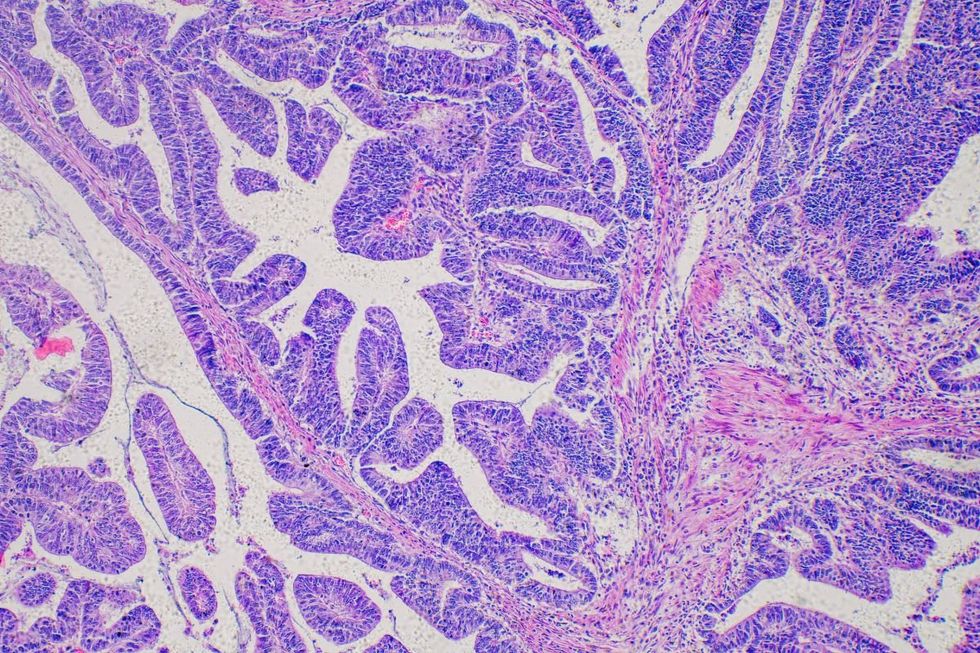

Barrett's Oesophagus can lead to oesophageal cancer

|GETTY